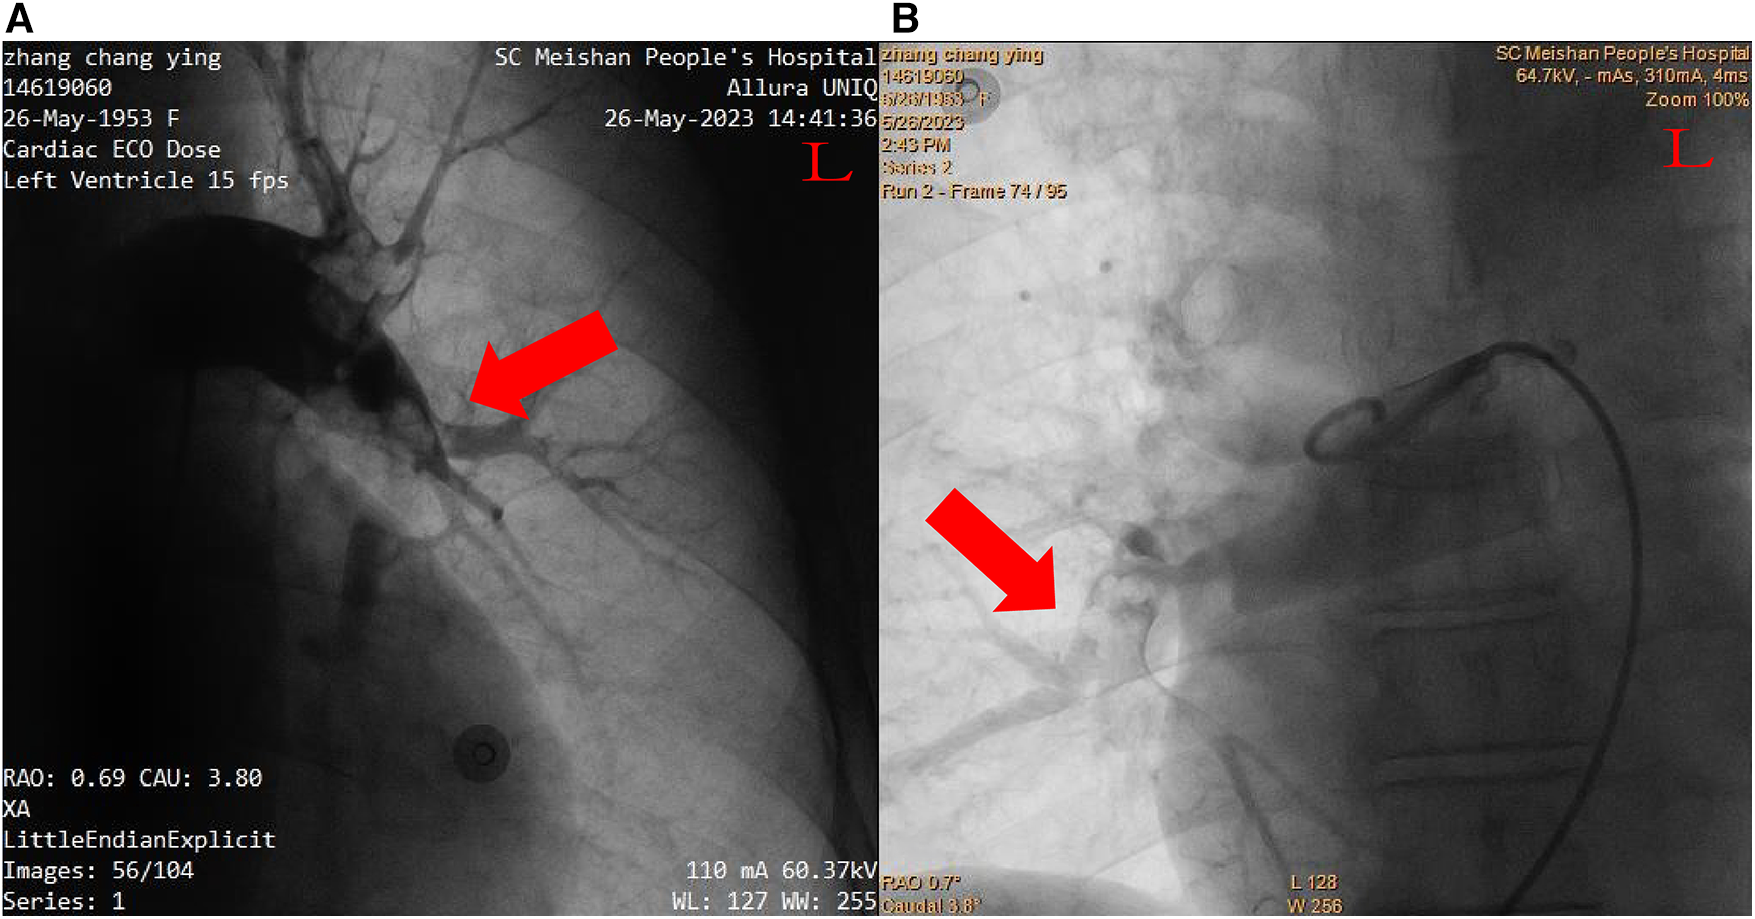

After inserting a 6-French (Fr) flex introducer sheath into the right femoral route, a 6-Fr pigtail catheter was advanced over a 0.035-inch guidewire to reach the pulmonary trunk. The catheter-directed pulmonary angiogram confirmed simultaneous filling defects of the right and left pulmonary arteries, especially of the left PA with large saddle emboli (Figure 2). Since regular percutaneous catheter-directed systems of PE were unavailable in our hospital, the Export Aspiration Catheter (EAC; Medtronic Corporation, Sunnyvale, CA, USA) with 1.37 mm (0.054-inch) aspiration lumen, which is widely used in PCIs for establishing antegrade flow before culprit vessel stenting, was used to remove pulmonary large clots through aspiration mechanisms. After dilatation of the Sprinter balloon (2.5 × 20 mm; Medtronic, Inc., Minneapolis, MN, USA) in the distal part of the right middle-pulmonary artery, the EAC was inserted for thrombus aspiration. With the limited diameter of the EAC, thrombus aspiration seemed to be ineffective, and only a small amount of thrombus was removed. In total, 1 million IU of urokinase was delivered through the EAC, a significantly lower dose than the standard treatment indicated for systemic thrombolysis, with a loading dose of 4,400 IU/kg, followed by 4,400 IU/kg/h over 12–24 h (1). Thus, the Guidezilla GEC with a larger inner diameter (0.067 inches, 1.71 mm), which allows more room for aspiration, was considered to be the optimal alternative to remove the thrombosis clot. Rather unexpectedly, the Guidezilla GEC captured several fresh thrombi in the bilateral PA and successfully aspirated and brought them out from the catheter. Subsequently, 1 million IU of urokinase were bolus injected as in situ thrombolytics in the left main pulmonary artery through the Guidezilla GEC. The pigtail catheter-directed pulmonary angiogram demonstrated a significant reduction in the size of the thrombus and the reperfusion in the bilateral PA was substantially improved (Figure 3).

Figure 2

Pulmonary angiogram. (A) Left pulmonary arteries. (B) Right pulmonary arteries.

Figure 3

Postcatheter-related treatment. (A) Left pulmonary arteries. (B) Right pulmonary arteries.